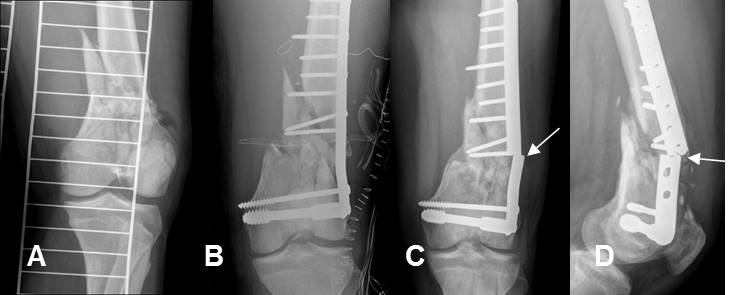

Fig 119. Fractura periprotésica.

A: Rx AP. Prótesis en la cabeza femoral.

B: Rx AP. Fractura oblicua y subtrocantérica, con angulación en varo.

C: Rx AP. Fijación de la nueva lesión con placa y cerclaje.